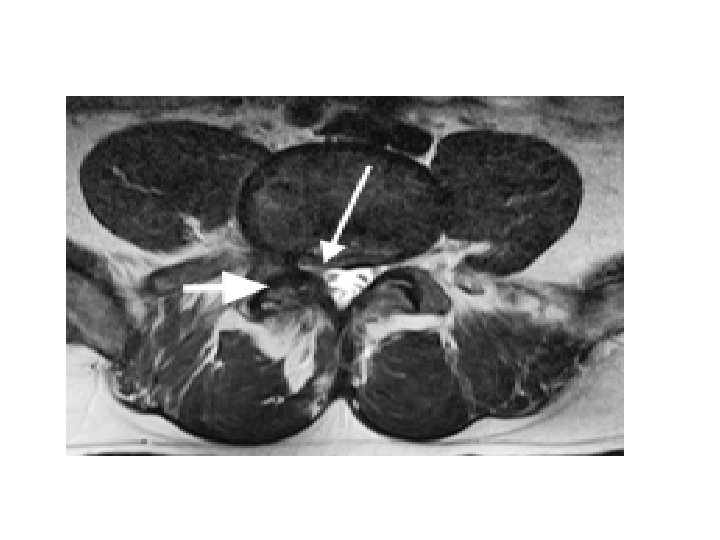

• Pathophysiology : Compression can lead to either foraminal stenosis mainly , lateral recess stenosis or rarely central stenosis. § foraminal stenosis : mainly : – Adult isthmic spondylolisthesis at L 5/S 1 often leads to radicular symptoms caused by compression of the exiting L 5 nerve root in the L 5 -S 1 foramen. compression can be caused by : • hypertrophic fibrous repair tissue of the pars defect • uncinate spur formation of the posterior L 5 body • bulging of the L 5/S 1 disc § lateral recess stenosis • caused by facet arthrosis mainly or hypertrophic ligamentum flavum. § central stenosis • rare due to fact that these slips are usually only Grade I or II

- neurologic symptoms caused mainly by central and lateral recess stenosis and to a less degree foraminal stenosis. § Central and lateral recess stenosis : • degenerative slip at L 4/5 will affect the descending L 5 nerve root in the lateral recess. - caused by slippage, hypertrophy of ligamentum flavum, and encroachment into the spinal canal of osteophytes from facet arthrosis.

• Imaging : - X-ray : AP , lateral , oblique * on lateral view : forward slip is evident. * on oblique view : gap in pars interarticularis. - MRI : to evaluate impingement of neural elements. - CT : for bony pathology. - CT myelogram : when MRI contraindicated.